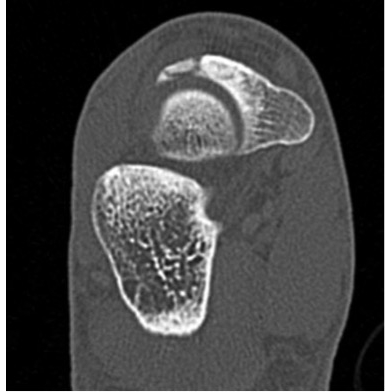

CT Scan Right Foot 5/24/13 Case Photo #3 : 8 x 3 x 4 mm ossification from the proximal dorsal aspect of the navicular consistent with remote avulsion fracture. 6.5 mm linear radiolucency from the dorsal navicular bone at donor avulsion site tracking medially with surrounding sclerosis. This is consistent with chronic incomplete obliquely oriented navicular stress fracture.

Case Photo #4